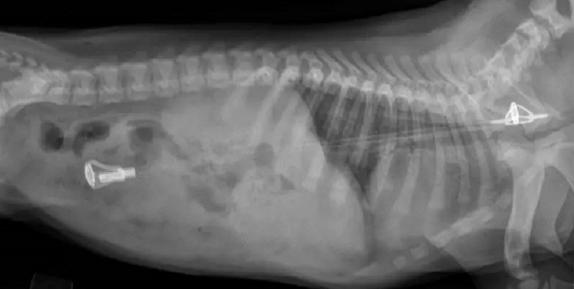

离谱!狗还能变成萤火虫?

什么东西在发光 ——手电筒啊!

吞进了跟身体差不多长的鱼竿

这拉猪到底是怎么办到的??